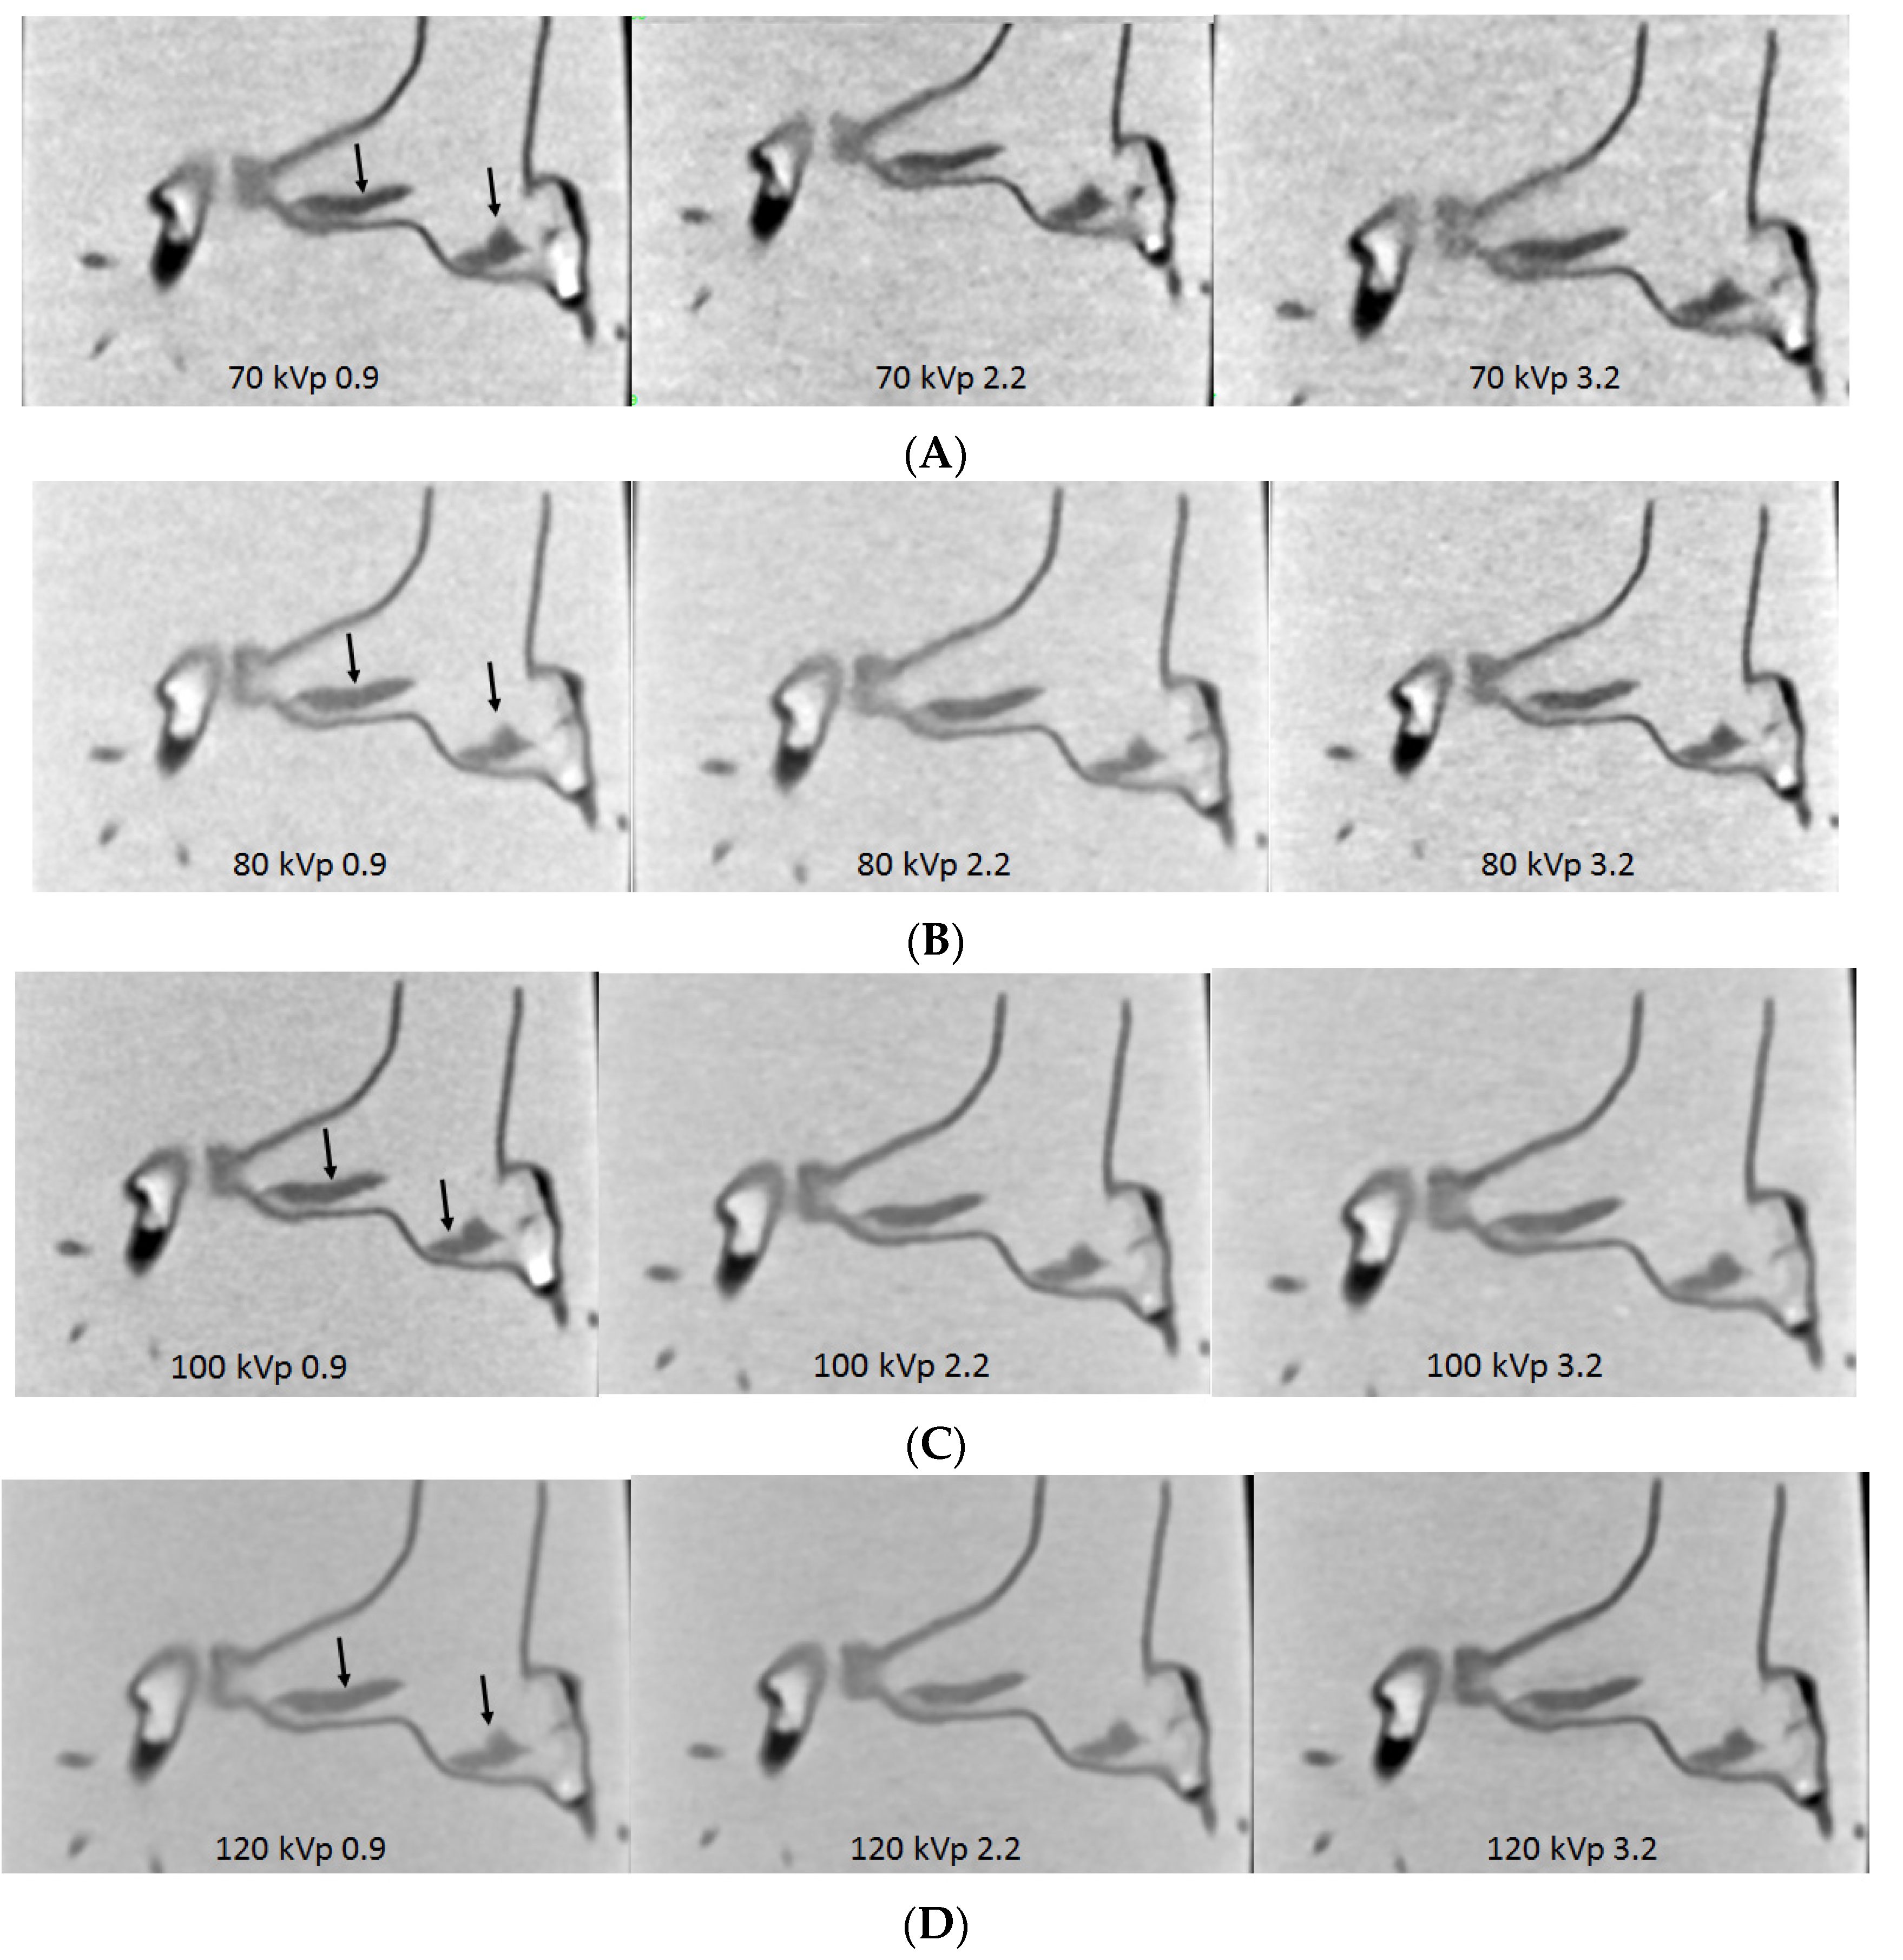

- Sun, Z.; Ng, C.K.; Squelch, A. Synchrotron radiation computed tomography assessment of calcified plaques and coronary stenosis with different slice thicknesses and beam energies on 3D printed coronary models. Quant. Imaging Med. Surg. 2019, 9, 6–22. [Google Scholar] [CrossRef] [PubMed]

- Sun, Z.; Aldosari, S. Three-dimensional printing in medicine: Opportunities for development of optimal CT scanning protocols. Australas. Med. J. 2018, 11, 529–532. [Google Scholar] [CrossRef]

- Aldosari, S.; Jansen, S.; Sun, Z. Optimization of computed tomography pulmonary angiography protocols using 3D printed model with simulation of pulmonary embolism. Quant. Imaging Med. Surg. 2019, 9, 53–62. [Google Scholar] [CrossRef] [PubMed]